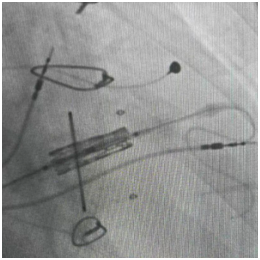

球囊扩张术

手术台上,心脏大血管外科陈文生团队通过细致的影像引导,将球囊送至原有瓣膜处进行扩张,随后将新的生物瓣精准释放在预定位置。最后,在心脏稳定的状态下,顺利植入了永久起搏器。整个过程中,患者生命体征平稳。